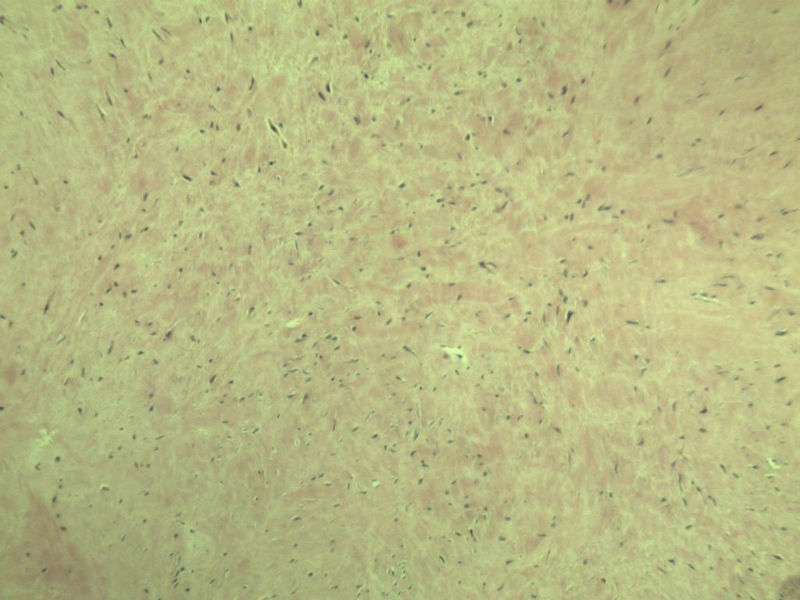

男,51岁, 4月前患者无意中发现右腘窝一包块,约核仁大小无疼痛, 4月来包块进行性生长

灰褐类圆形包块一个,直径 5 cm,切面灰白,实性,编织状。 请各位老师看看 是什么? 谢谢!